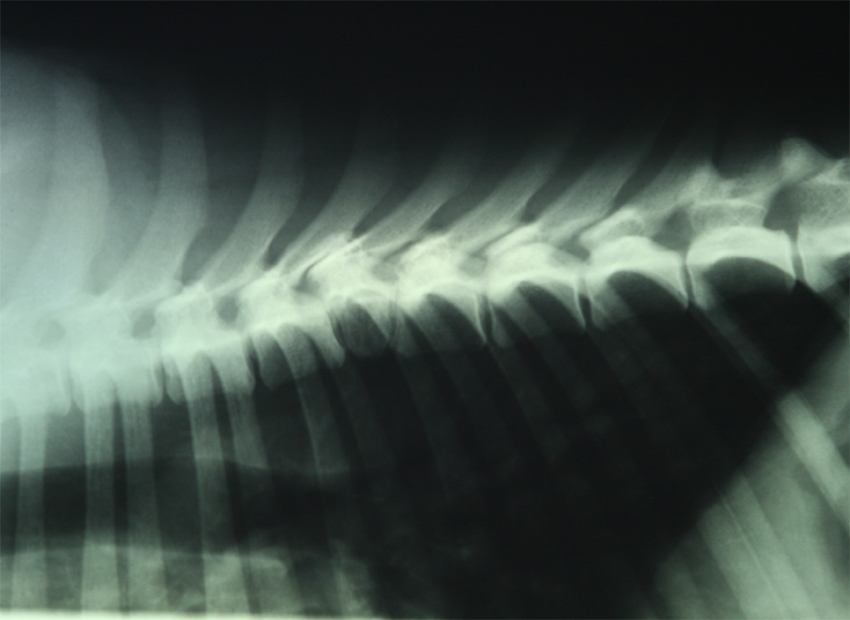

Viralliset selkäkuvat

Selän spondyloosi

SP0

(puhdas)

(8/13 ja 1/16)

****

SP1

(lievä)

T13, L1-L3 ja S1 -väleissä 2 siltaa, loput pieniä alkuja

(11/20)

Rintarangassa spondyl.löydös, kaventunut nikamaväli, skoliosis

Polvet ja olkapäät kuvattu terveiksi. Selkämuutos: hemivertebra **)

**) Sonetti kuvattiin 15.7.13 ell Kari Ventelän toimesta.

Kuvatuissa nivelissä ei havaittu muutoksia, mutta rintarangan 6.nikama

on kiilan muotoinen. Ventelän mukaan ko. muutos ei tule aiheuttamaan oireita

ns. kotikoiralle, mutta esim. suojelukoiralle ko. muutoksella voisi olla haittaa.

Pyysin myös pieneläinsairauksien erikoiseläinlääkäri Anu Lappalaisen mielipiteen muutoksesta

sekä sisarusten jalostuskäytöstä: "Todennäköisesti ei tule vaivaamaan koiraa (varsinkin, jos kotikoira),

jos ei selässä muita muutoksia. En muista nähneeni belgeillä eli ei ainakaan ole yleinen. Kyllä mielestäni

sisaruksia voi käyttää, jos selät ok ja tämä pentueen ainoa tämmöinen."